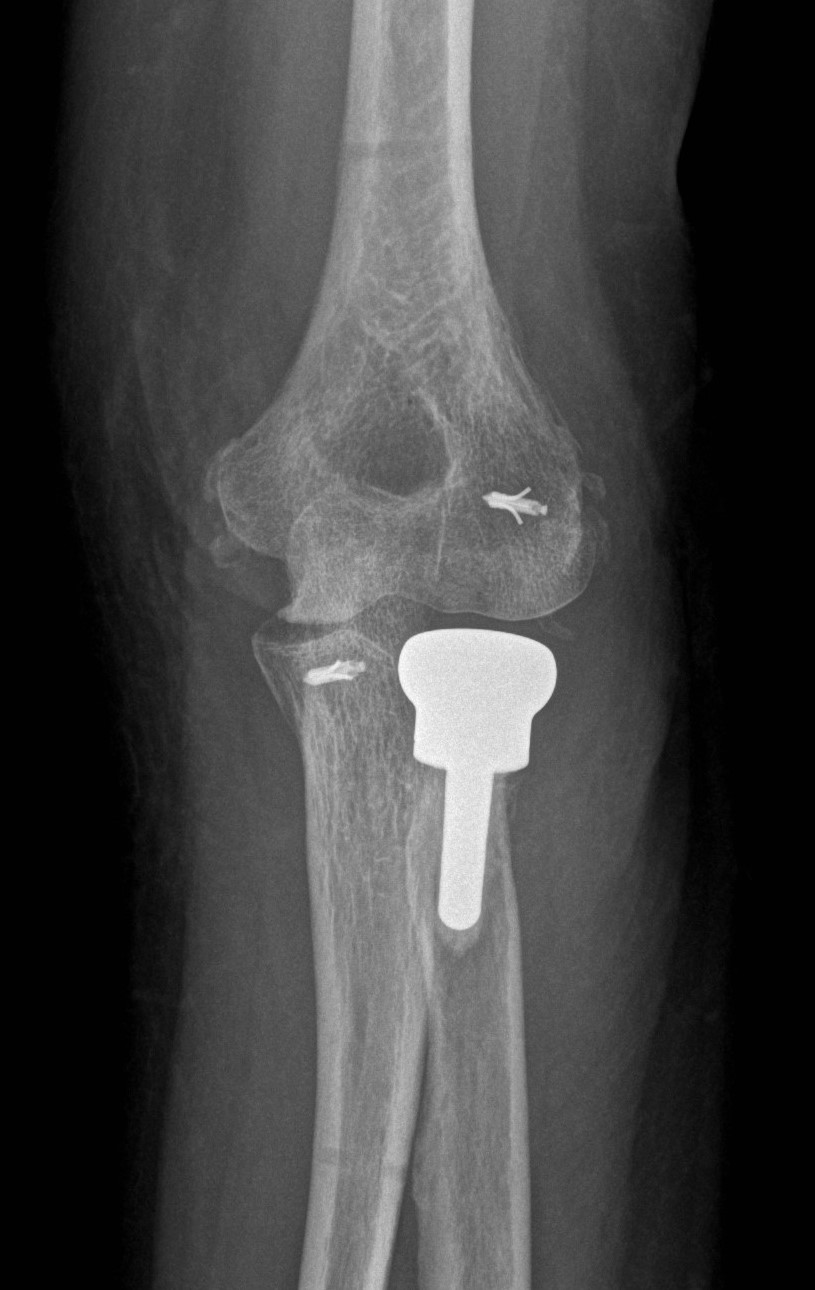

Wir stellen den Bewegungsumfang wieder her, ersetzen Bänder bei Instabilität, fühlen Knochendefekte bei posttraumatischen Zuständen auf, korrigieren die Achse des Ellenbogens und implantieren Endoprothesen.